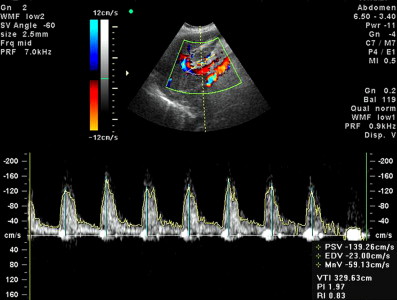

• проанализирует структуры сердца (камеры, клапаны, стенки предсердий, желудочков, околосердечную сумку, скорость движения крови)